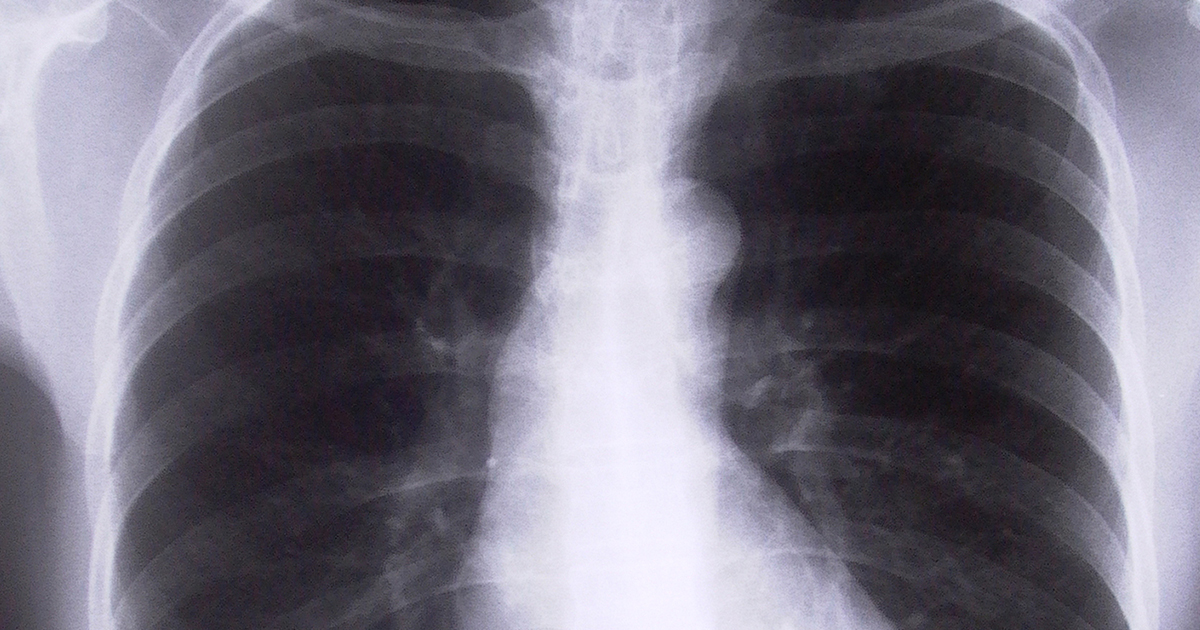

The worker, (who for confidentiality reasons, we will call ‘B’) suffered a crush injury to his upper body in 1999. In 2014, he collapsed at home and was hospitalised and a pacemaker was inserted into his chest. The pacemaker caused an infection of the heart muscle because the pacing wire was pushed too far in. The pacemaker lead was replaced in 2017, and a further claim for the costs of that surgery were made and rejected by the compensating authority. The claim was based on damage to the heart having been caused in 1999 by a “hydraulic compression” of a node within the heart.